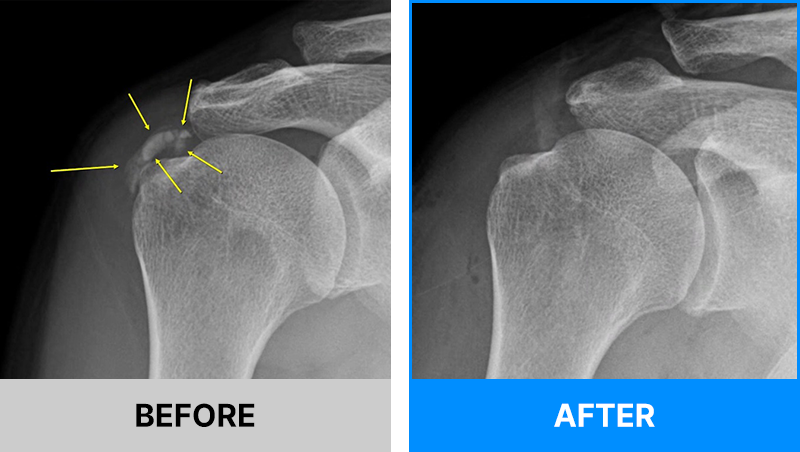

어깨의 석회는 그 시기에 따라 액체형과 고체형 그리고 혼합형으로 존재할 수 있습니다.

액체형 석회를 흡인하는 것은 어디에서나 가능합니다. 하지만 고체형 그리고 혼합형 제거에는 많은 노하우가 필요합니다.

서울거탑정형외과에서는 고체형 석회를 잘게 분쇄하여 뽑아내는 독자적인 기술과 노하우를 보유하고 있습니다.

해당 시술은 석회의 위치를 초음파로 정확히 확인한 뒤,정교한 기술로 진행되는 비수술 치료입니다.

그만큼 의료진의 숙련도와 경험이 매우 중요하므로, 풍부한 시술 경험을 가진 정형외과 전문의를 통해 치료받는 것이 좋습니다.

서울거탑정형외과에서는 풍부한 노하우로 초음파를 통해 정확히 석회를 확인 후 고체형일지라도 미세하게 분쇄하여 제거가 가능합니다.

95%이상 석회 제거가 가능합니다.